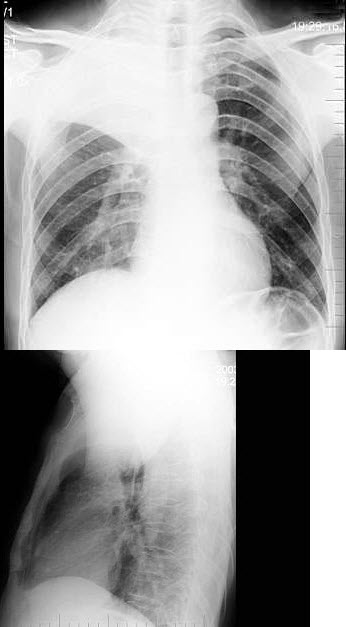

22、单项选择题

患者,女,46岁,胸闷气短1月,伴全身乏力,咳嗽,发热。胸片示:中上纵隔增宽,右缘呈波浪状改变。白细胞:8.5×10/L。

最可能的诊断是()